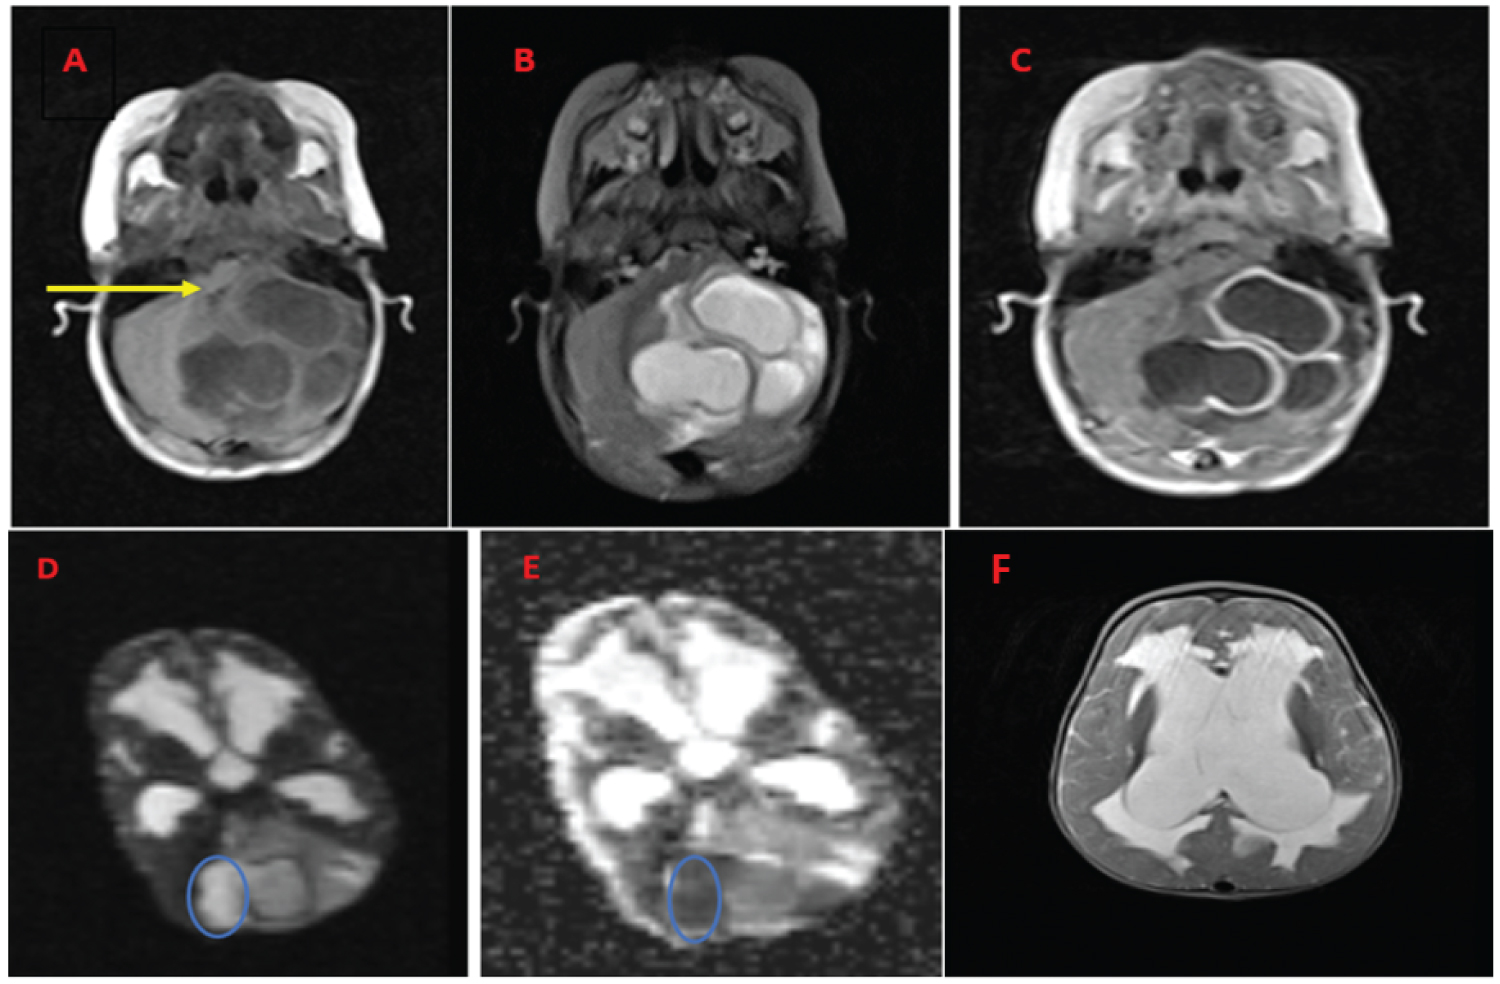

Brain Magnetic Resonance Imaging (MRI) showed three ring enhancing cystic lesions occupying the vermis and the left cerebellar hemisphere. The lesions were associated with surrounding cerebellar edema and obstructive hydrocephalus with transependymal edema (Figure 1). On T2-weighted sequence, DS was visualized as a narrow strand of tissue passing obliquely from the midline cyst wall to diploic space of occipital bone which was a significant clue to suspect the possibility of infected IDC (See Figure 2).

Figure 1: A) Brain MRI showing cerebellar abscess associated with posterior fossa dermoid cysts causing obstructive hydrocephalus. The axial images show T1 hypointense; B) T2 hyperintense three cerebellar cysts causing surrounding cerebellar edema and mass effect on the 4th ventricle; C) On T1 contrast imaging the cysts' wall has enhancement which is not complete in the cyst located at midline; D) The medial part of the midline cyst has diffusion restriction, being bright on DWI sequence; E) Dark on ADC map; F) The axial T2-weighted shows markedly dilated lateral ventricles with trans ependymal edema due to the obstructive hydrocephalus. View Figure 1